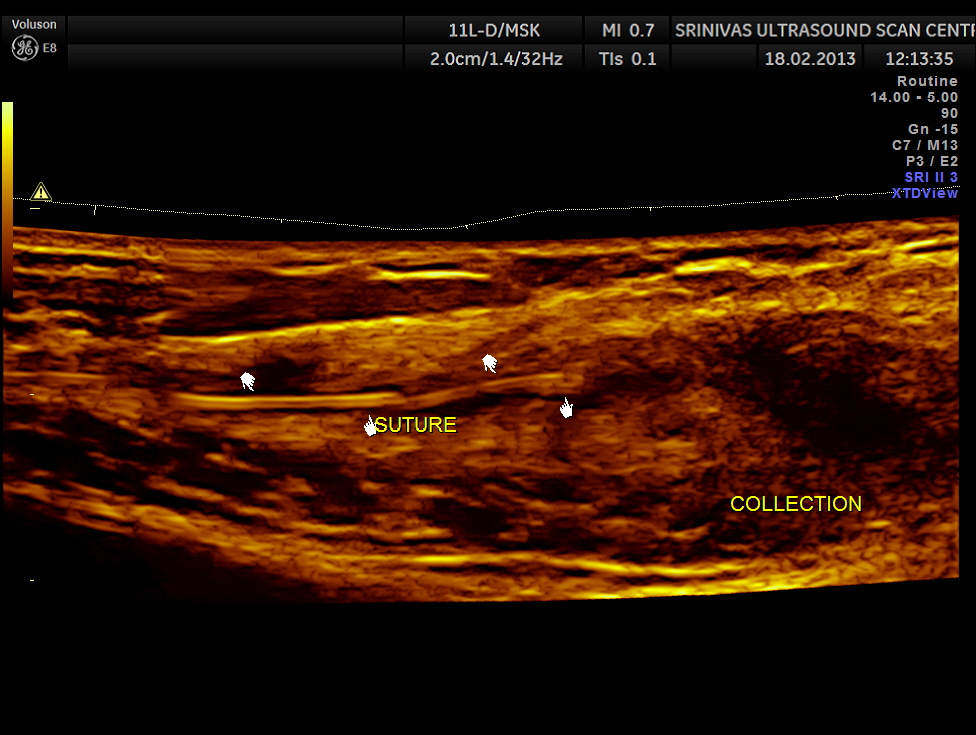

She was being evaluated for complaints of purulent discharge on and off from the scar tissue with pain.

Her routine abdomino pelvic ultrasound scan was normal. The following pictures are acquired with a high resolution 11Mhz transducer.

This revealed unabsorbed suture and irregular collection